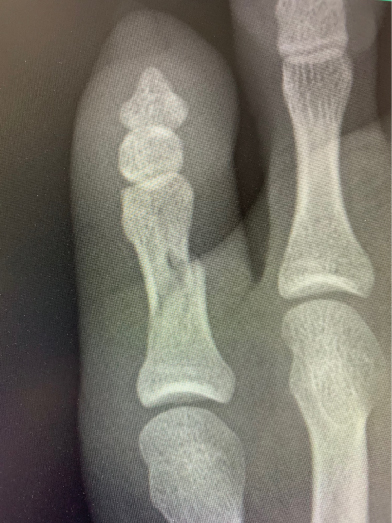

当院院長は「ほねつぎ」として圧倒的な症例数の骨折や脱臼、捻挫等を手術無しで治してまいりました。その技術を後進に残すために指導も行っております。

手術が必要な骨折など全骨折中の数%しかありません。

傷も残らず患者様の体にも負担が軽く、手術よりも早期回復が見込めるため病院からの依頼もあります。

骨折/足趾骨骨折

整復後